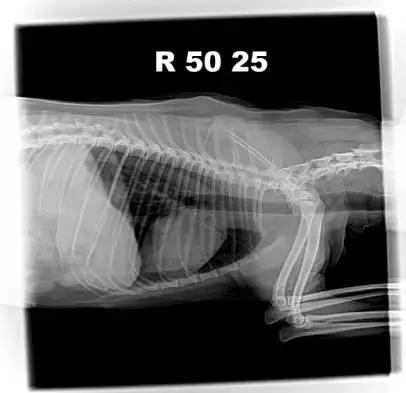

2.4.1 胸腔DR

胸腔DR腹背位/右侧位检查,影像未见明显异常。

25日腹背位胸腔DR影像

25日右侧位胸腔DR影像